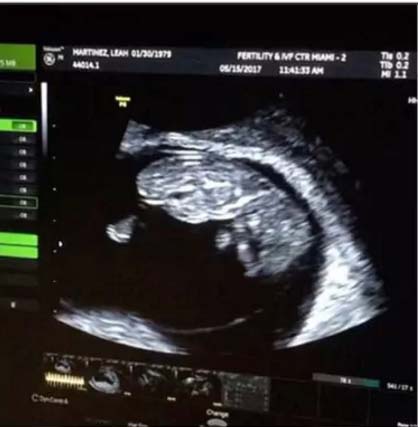

"Hoy se cumplen casi 18 semanas de aquel día, que Dios me daba la posibilidad de cumplir el sueño de mi vida. ¡Estoy tan feliz, agradecida y emocionada que no tengo palabras para expresar lo que siente mi corazón en este momento! Todo por vos, mi bebé’, escribió Luciana Salazar en su cuenta en Instagram junto con el video de la ecografía, a una semana de su separación del economista Martín Redrado. La noticia conmocionó al mundo de la farándula porque cuando explotó la bomba, se pensó que era ella la que estaba embarazada; hasta que se confirmó que será madre por vientre subrogado de una nena que se llamará Matilda y según anunciaron en Intrusos tendrá como padrinos: al periodista Marcelo Polino y Ana Rosenfeld, su abogada; además, ayer el doctor Fernando Ackerman dialogó con Los Angeles de la Mañana sobre el procedimiento que se llevó a cabo en Miami.

El deseo de ser madre Luli, de 37 años, no es nuevo. Sin embargo, esta vez, decidió concretarlo, tras congelar sus óvulos en 2016. Y la eco pertenece a la madre subrogante, Leah Martínez, de 38 años, en la clínica especializada Fertility & IVF Center of Miami el pasado 15 de mayo, al cumplirse los 3 meses de gestación. La portadora de la beba recibirá 60 mil dólares, según Revista Pronto.

Después de colgar el clip original; ayer, la rubia cambió su posteo en Instagram, quitando los datos de los estudios y dejando la imagen de captura y el texto. ¿Por qué? Para resguardar la intimidad, quizás, aunque tarde…